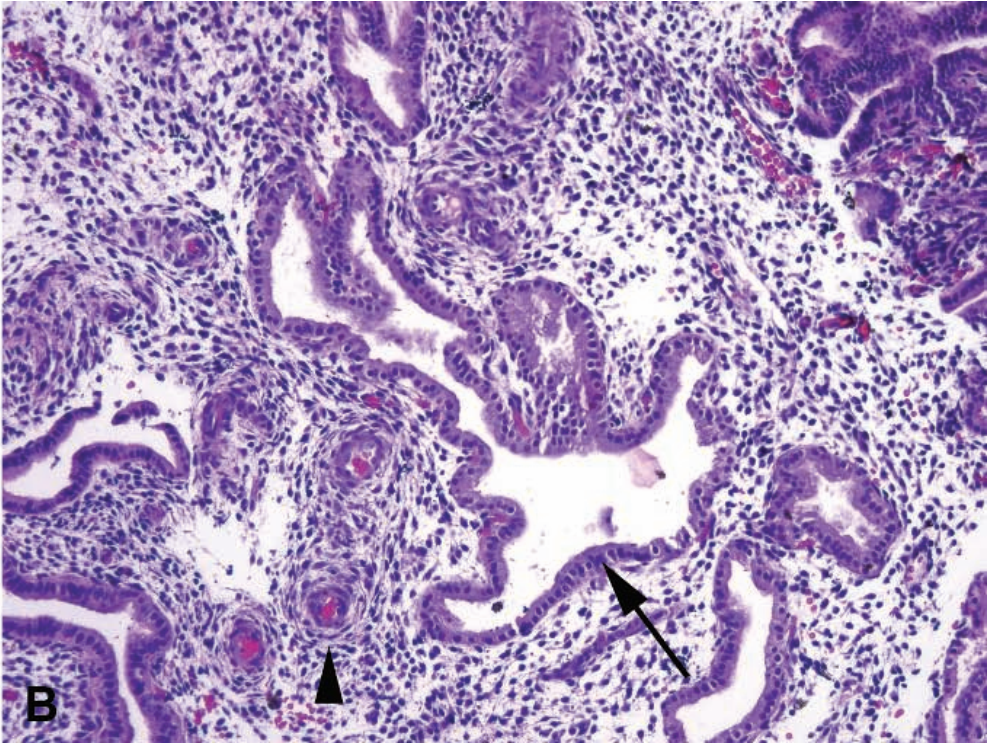

13

Q

A

Chronic endometritis

Arrow: Spindly, swirling blue stroma

Arrowhead: Proliferative endometrium

Describe the morphology of acute and chronic endometritis.

Acute: Microabscesses and epithelial destruction (neutrophils alone could just be menses)

Chronic: Plasma cells, with blue spindled stroma and more lymphocytes.